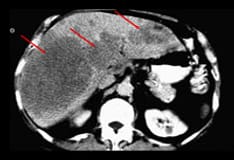

Background